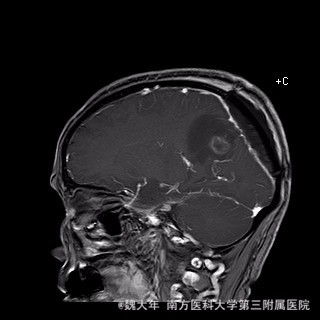

52岁,女性,因“反复头痛10余年,加重1年”入院。患者10余年前无明显诱因始出现头痛,表现为全头发作性胀痛,反复发作,无伴头晕、恶心,无呕吐、肢体抽搐,自行服药(具体不详)及休息后缓解,未予特殊处理。1年前患者觉头痛逐渐加重,以右顶部为甚,劳累或日晒后加重,无头晕、视物旋转,无恶心、呕吐,无发热、寒战,休息或平躺后症状稍有缓解,自行服药不能改善,至当地医院就诊,查颅脑MRI和CT提示“右侧顶部脑膜瘤”。

行“右顶开颅右顶部矢状窦旁脑膜瘤切除术”。取右顶马蹄形手术切口 ,颞侧翻开皮瓣,电刀切开骨膜,中线矢状缝上前、后极各钻一孔,颞侧后方钻一孔,铣刀铣一长方形(7*6cm)骨瓣,见硬膜表面较多点状渗血,予充分止血,悬吊硬膜。 显微镜下切除肿瘤:沿肿瘤边缘剪开硬膜后,见一大小约5*5*6cm肿瘤,沿硬膜内侧面呈匍匐状生长,边界与脑组织有蛛网膜分隔,质地较韧,基底与矢状窦关系密切,靠内侧与大脑镰粘连紧密,血供丰富。仔细分离肿瘤与脑组织的粘连,全切除肿瘤。肿瘤基底与矢窦粘连紧密,并破坏矢状窦侧壁,予低功率电刀反复烧灼,直至肿瘤无明显血供表现。严密止血后常规关颅。

术后1周复查头颅MR未见明显肿瘤残留,拆线后出院。